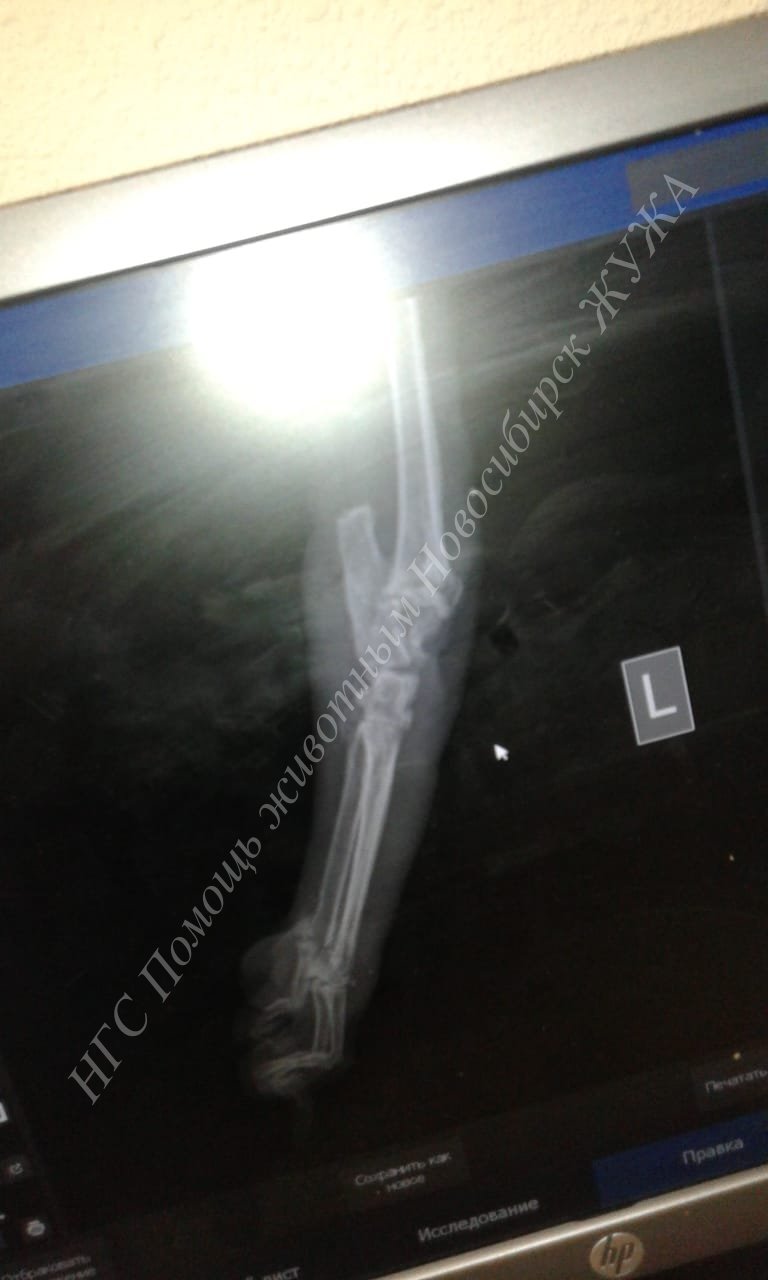

Вчера мы с Жуженькой стриглись, и ездили в Ветлекарь, у нашей девоньки большая и серьёзная проблема с пролежнем на задней лапке, он стал больше буквально за несколько дней, сустав опух и видно кость, выглядит всё очень страшно. Я так корю себя, что не бросила все проблемы в приюте у нас и не поехала с ней в клинику раньше.

У Жуженьки прям до кости всё оголилось, я когда увидела, мне стало плохо, врач сказала, что остеомиелита пока нет, но он возможен. У Жужи паталогическая подвижность сустава в этом месте, и выскочила косточка, хрящ воспалён, т.е. возник гнойный артрит и из сустава вытекает синовиальная жидкость.

Прописали очень сильную дозу Амоксиклава, чтоб он проник в кость, я купила аналог, и вот мазь, которую нам ещё в клинике заложили, она 500р стоит тюбик, взяла сразу в клинике. Нужно прям обильно мазать и делать перевязки, особым способом бинтовать, своего рода кокон вокруг лапки, прям много много бинта, 2 рулона уходит за раз. В день делать 2 перевязки.

Врач сказал, что если не будет положительной динамики в течении недели, то лапку надо ампутировать

, я когда это услышала, в глазах потемнело. Я очень хочу спасти лапу!

Вчера потратила на рентген, перевязки, приём и гель 3000руб., + 1100руб. на стрижку, и сегодня ещё купила на 713руб. лекарств и бинтов стерильных, которые будут к ране примыкать, и не стерильных, сверху обвязывать кокон.